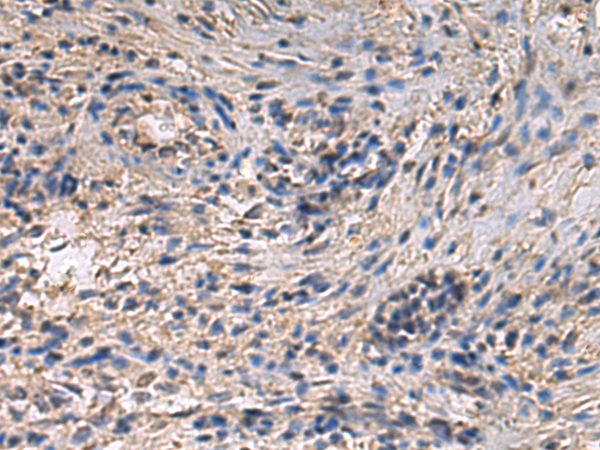

分类: 科研抗体货号: P06610别名: ENA; MENA; NDPP1应用: IHC反应种属: Human, Mouse